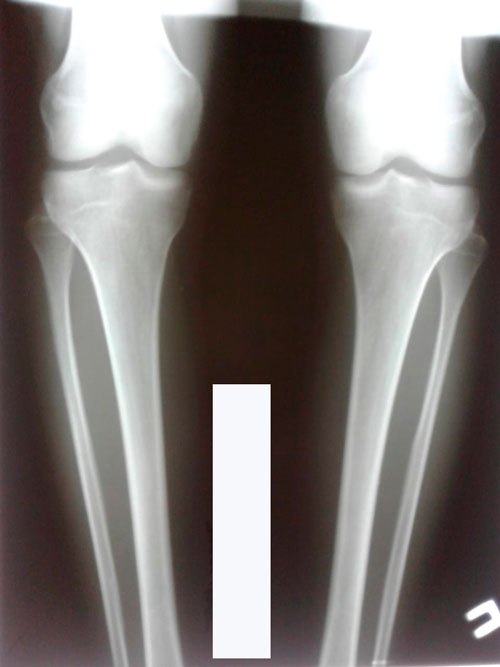

Исходник - 22 года. Павлодар.

Дата операции - 19.06.2018г.

Ротация справа.